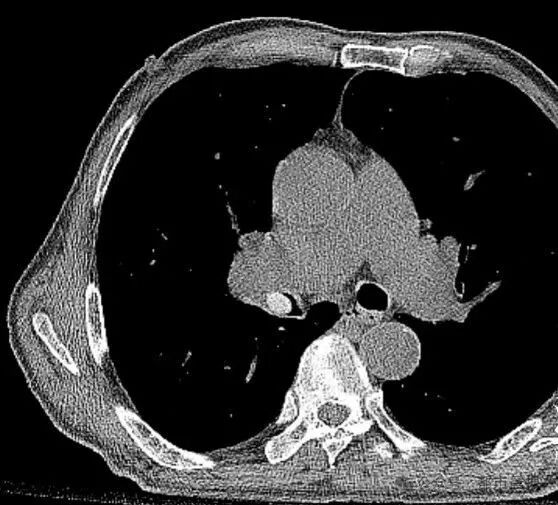

另一例83岁女性患者更凶险,因帕金森病导致吞咽功能减退,她误吸枇杷核后突发心肺骤停。经抢救发现果核深嵌气道,最终通过高难度气管镜手术取出。柳主任指出:“这类基础病患者一旦发生气道异物,死亡率可达普通人群的3倍以上。”

枇杷核卡肺9天 七旬老人千里求医 原来他吞枇杷时核子“走错路”,直接滑进右肺中间支气管。当地医院因担心患者身体条件太差,医生不敢冒险做“取核手术”。于是家人连夜带着张大爷赶到上海,前往瑞金医院就诊。 在进行充分的准备后,呼吸科医生成功对张大爷实施手术,仅用5分钟便将约1.5厘米的枇杷核完整取出。此时,这颗枇杷核已经卡在张大爷的肺里长达整整9天。